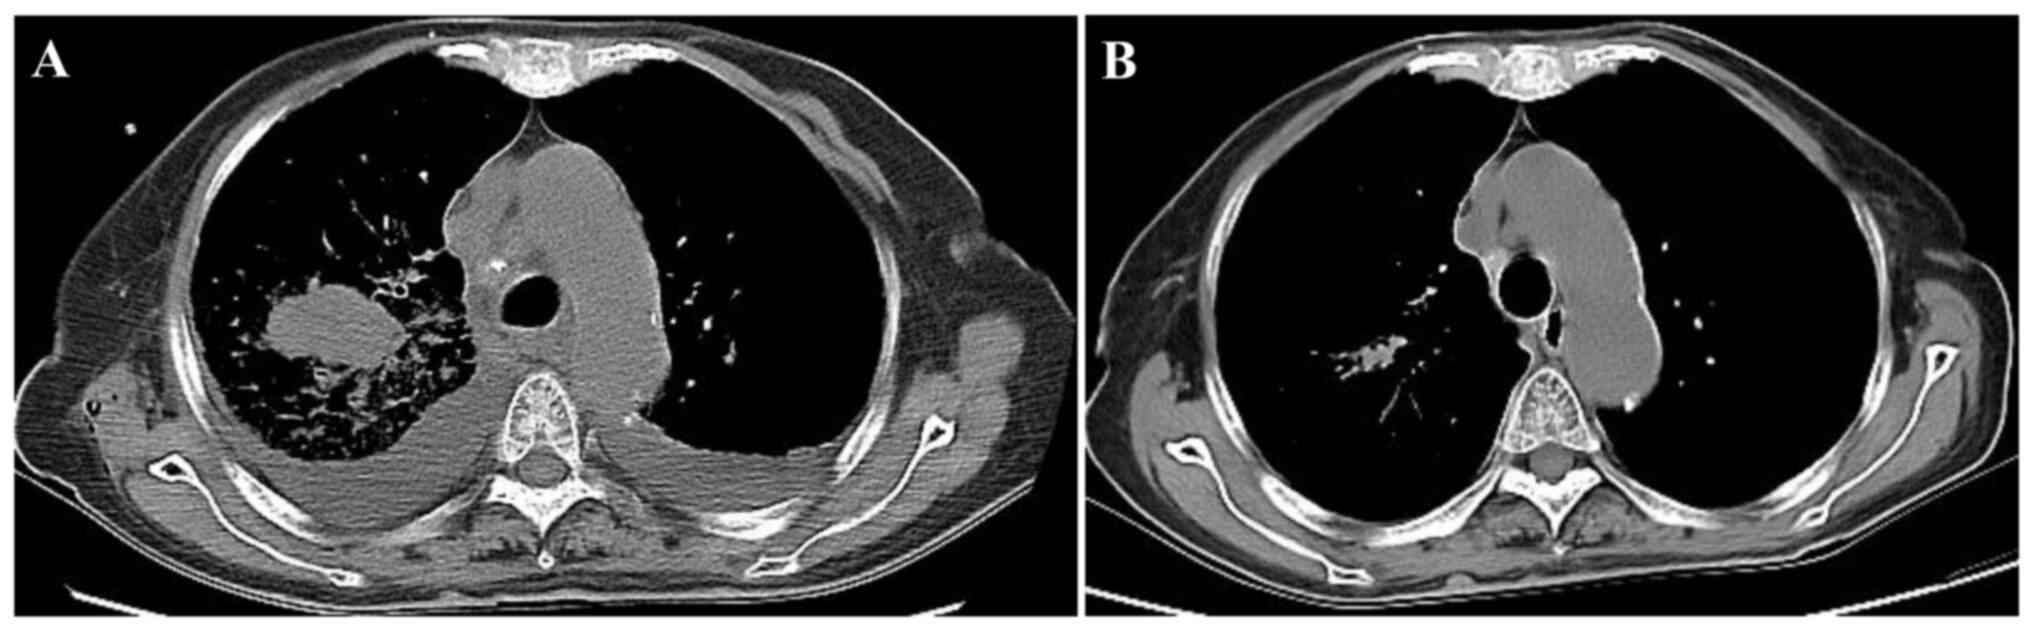

Immunohistochemistry was performed using the aforementioned biopsy sections. Sections were heated at 65°C for 120 min and then dewaxed by incubation with xylene for 3 min (six times). Sections were rehydrated using a decreasing alcohol series and antigen repair was performed using EDTA repair solution (pH 9.0; Fuzhou Maixin Biotech Co., Ltd.) by heating in a pressure cooker to boiling and then being kept warm for 20 min. Sections were incubated with 3% H2O2 for 10 min and then rinsed with PBS for 3 min to block endogenous peroxidase activity. Sections were incubated with ready-to-use primary antibodies against HMB45 (cat. no. MAB-0098; Fuzhou Maixin Biotech Co., Ltd.), SOX-10 (cat. no. MAB-0726; Fuzhou Maixin Biotech Co., Ltd.), S-100 (cat. no. Kit-0007; Fuzhou Maixin Biotech Co., Ltd.), Melan-A (cat. no. JY-0083; Dako; Agilent Technologies, Inc.) and Ki-67 (cat. no. JY-0222; Dako; Agilent Technologies, Inc.) for 1 h at room temperature. Washing was performed using PBS. Sections were then incubated with EnVision Detection Systems Peroxidase/DAB, Rabbit/Mouse (cat. no. K5007; ready-to-use; Dako; Agilent Technologies, Inc.) secondary antibodies for 30 min at room temperature. DAB from the aforementioned secondary staining kit was added for detection. Sections were counterstained with hematoxylin for 2 min at room temperature and imaged using a CX31 light microscope (Olympus Corporation). Immunostaining revealed melanin pigmentation and malignant cells that were positive for HMB-45, Melan-A, SOX-10, S-100 and Ki-67 (>20%) and negative for CKAE1/AE3 (cat. no. JY-0047), CK5/6 (cat. no. MAB-0744), TTF-1 (cat. no. MAB-0677), CD-45 (cat. no. Kit-0024) and synaptophysin (cat. no. MAB-0742) (all ready-to-use; Fuzhou Maixin Biotech Co., Ltd.) (Fig. 4). Whole-body 18F-FDG PET-CT revealed a density anomaly in the mass in the right upper lung complicated by elevated glucose metabolism with a maximum standardized uptake value (SUVmax) of 24.7 and elevated glucose metabolism of the hilar/mediastinum lymph nodes with an SUVmax of 15.9 (Fig. 1B). There were multiple metastatic lesions in the kidney, liver and bones. On the 10th day following admission, genetic molecular testing for BRAF or NRAS mutations using PCR-Sanger sequencing was performed by the Clinical Molecular Diagnostic Center of Taihe Hospital, Hubei University of Medicine, and a BRAF V600E mutation was reported (Table I). Dabrafenib (150 mg orally twice daily) plus trametinib (2 mg orally once daily) was subsequently administered, and following 2 months of therapy, a chest contrast-enhanced CT scan revealed that the malignant melanoma mass in the right lung had markedly reduced in size (Fig. 5). The patient was followed up, 15 months to date, and remained in good health with no evidence of recurrence. However, close follow-up of the patient is ongoing.

Figure 5.

Chest contrast-enhanced CT scan before and after treatment. (A) Chest contrast-enhanced CT scan before treatment showed a mass in the right upper lobe pretreatment. (B) Chest contrast-enhanced CT scan showed that the mass had almost disappeared in the right upper lobe post-treatment. CT, computed tomography.

The optimal treatment for patients with PMML remains to be determined. For patients whose lesions are confined to the lung, lobectomy or pneumonectomy with lymph node dissection remains the first choice of treatment for PMML patients (14). In cases where surgery is not possible or not desired by the patient, chemotherapy, radiation and immunotherapy may be considered. The conventional preferred chemotherapy agent is dacarbazine, which is usually used in combination with immunotherapies such as interleukin-2 or interferon (15). Robert et al (16) performed randomized trials and reported that first-line treatment with dabrafenib plus trametinib led to long-term benefits in ~1/3 of patients who had unresectable or metastatic melanoma with a BRAF V600E or V600K mutation. Moreover, in two independent phase 3 trials (COMBI-d and COMBI-v) (17,18), treatment with the BRAF inhibitor dabrafenib (150 mg twice daily) plus the MEK inhibitor trametinib (2 mg once daily) improved overall survival in patients with unresectable or metastatic melanoma with BRAF V600E or V600K mutations (72% overall survival rate at 12 months). As in the aforementioned randomized trial, after 2 months of treatment, the mass in the upper lobe of the right lung and the mediastinal lymph node lesions in the present patient had almost disappeared, thus dabrafenib plus trametinib demonstrated therapeutic efficacy.